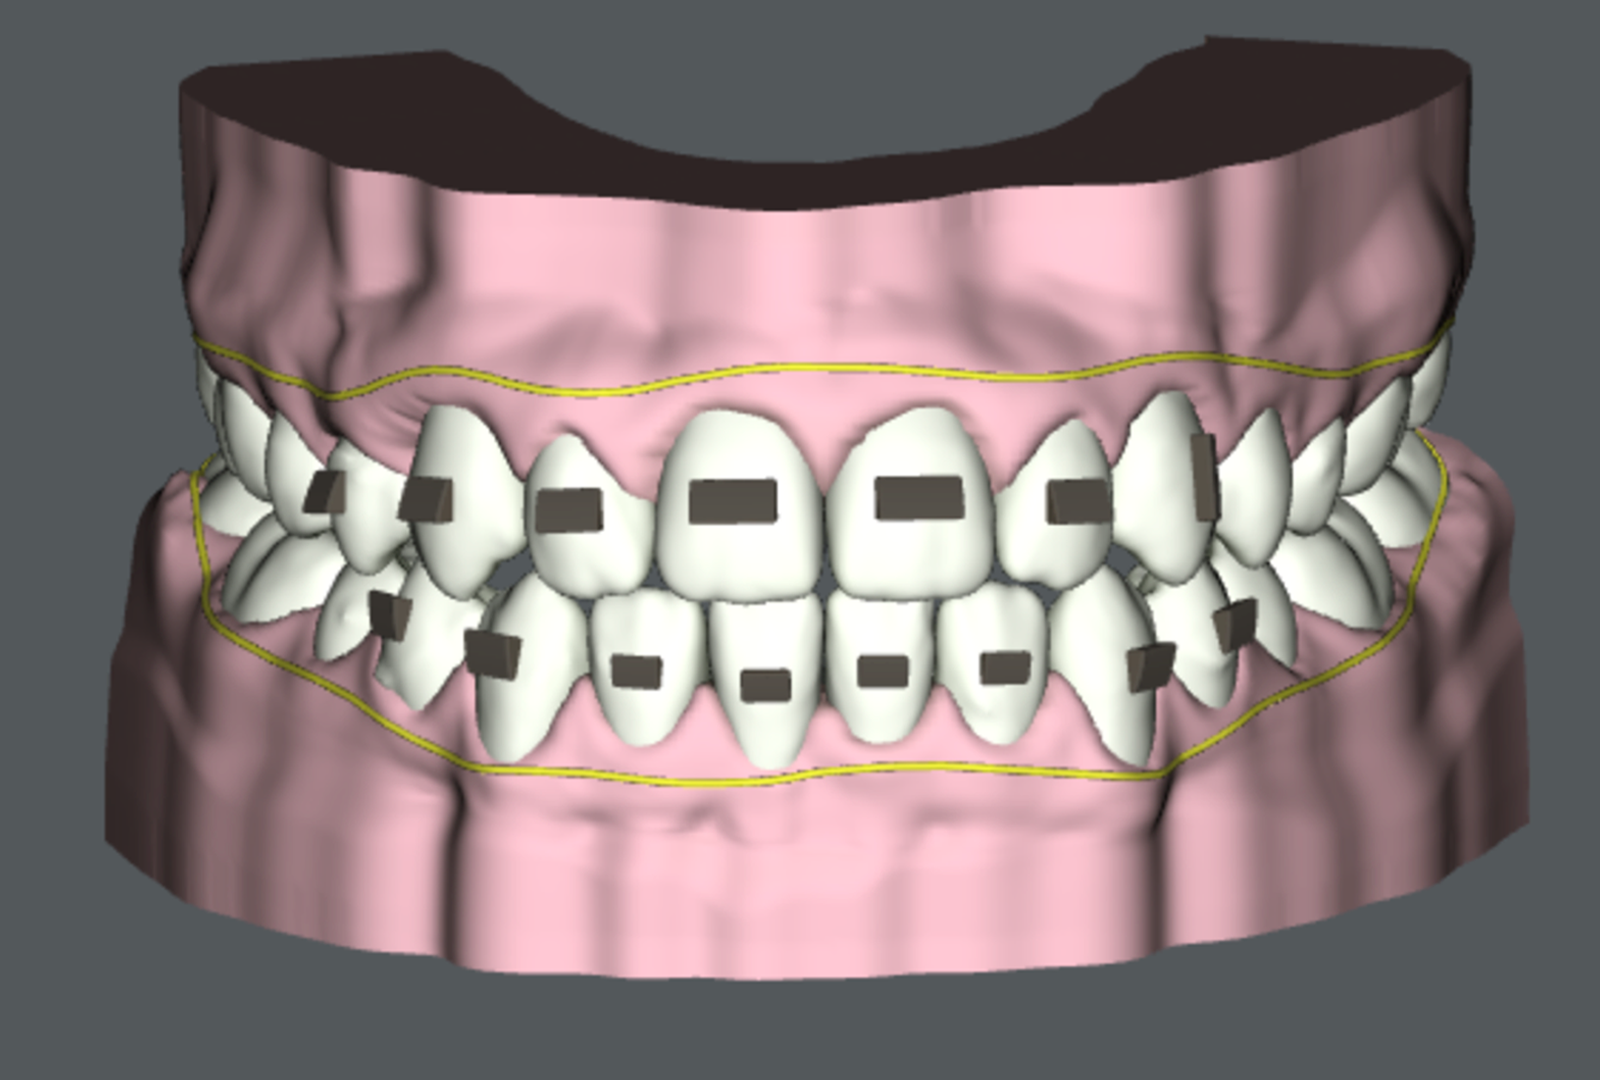

Deze twee cursussen op geavanceerd niveau zijn ontworpen om clinici vertrouwd te maken met de concepten en vaardigheden voor het diagnosticeren en het behandelplan voor zelfs de meest uitdagende casussen. Deelnemers leren hoe ze uitgebreide behandelplannen voor multidisciplinaire casussen kunnen benaderen, organiseren en uitvoeren. Aan het einde van de cursus zullen clinici zelfverzekerd zijn in het behandelen van complexere gevallen en in staat zijn om hulpmiddelen en hulpstoffen die de controle over de wortel- en lichamelijke bewegingen verbeteren, naadloos te implementeren. Aan het einde van deze serie hebben deelnemers een verhoogde expertise in CAT opgebouwd. CAT is een populaire keuze geworden voor patiënten die op zoek zijn naar een minder ingrijpende orthodontische optie, waardoor hun zorgstandaard wordt verbeterd, evenals de beleving van elke patiënt die hun praktijk bezoekt.

In deze cursus worden clinici begeleid door een branche deskundige door een reeks complexe casustypen om de beste werkwijzen te leren voor het plannen van de behandeling van dit soort casussen. Artsen leren hoe ze aligners kunnen combineren met de juiste hulpmiddelen als een doeltreffend middel om complexe orthodontische problemen aan te pakken.

Deze cursus is ontworpen om artsen op een gevorderd niveau bij aligner behandelervaring te helpen bij het plannen van de behandeling voor complexe, multidisciplinaire casussen. Artsen leren om de behandeling met succes en strategisch te plannen en hoe ze clear aligner-therapie kunnen integreren in andere vormen van patiëntenzorg. Restauratieve en prosthodontische behandelingen in combinatie met aligner-behandeling worden besproken, aangevuld met tips over de volgorde en overlap van zorgfasen om de behandeltijd te minimaliseren. Deze interactieve cursus volgt een casusgebaseerde benadering waarbij artsen de gelegenheid krijgen om meer te weten te komen over de behandelresultaten van de arts die de casus behandelde.